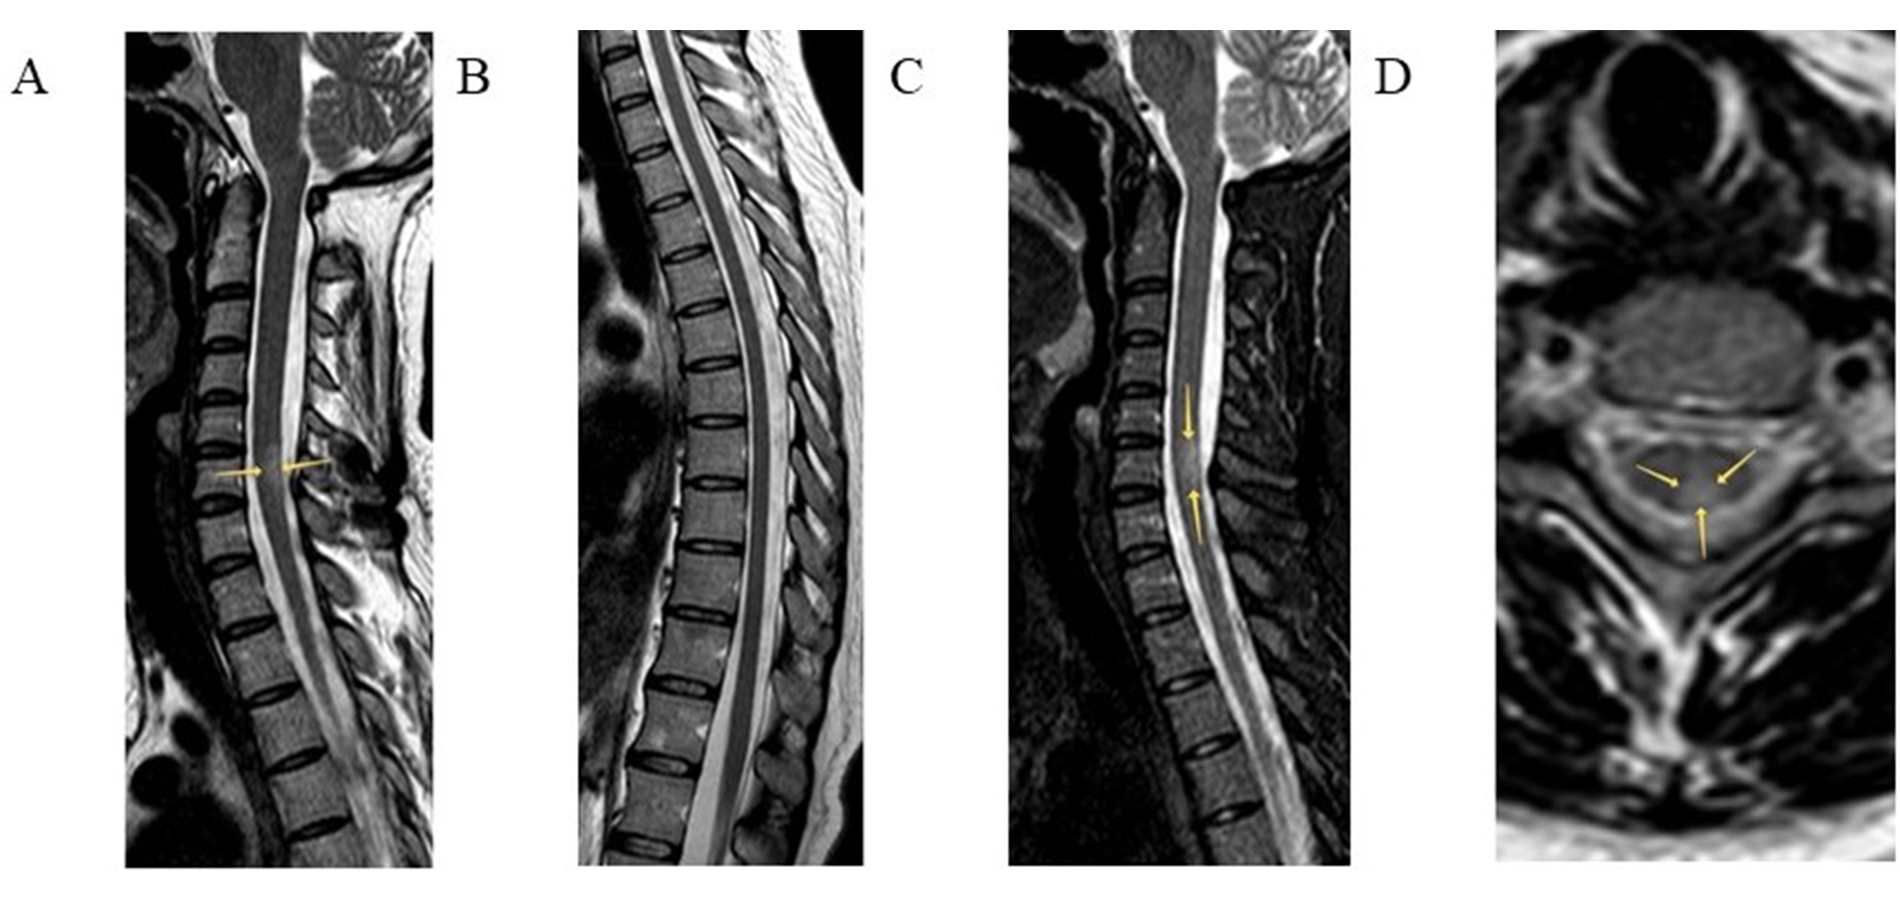

Spinal cord MRI of Patient 5. Sagittal T2 (A, B) and T2 weighted short tau inversion recovery (T2-STIR) (C) modes and axial T2 mode (D) are presented. Intramedullary, in the central and posterior regions of the spinal cord at the C6 level, a hyperintense lesion is visualized (arrows). Throughout the rest length, including the thoracic level, the spinal cord is intact, with homogeneous intensity of the magnetic resonance signal.